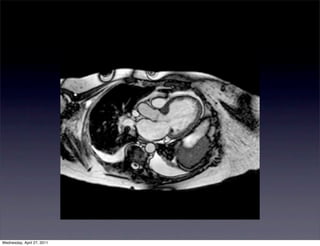

80 yo F with PMH of HTN, HLD, DM, CVA

with a history of continuous chest pain x 2

weeks. Patient was found to have a LBBB on

unknown duration. Cardiac enzymes were

negative. The patient was transferred to

WHC for further management.